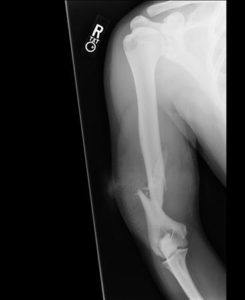

Focus on Fractures HW CPT Review for students RTD

NCCI Musculoskeletal